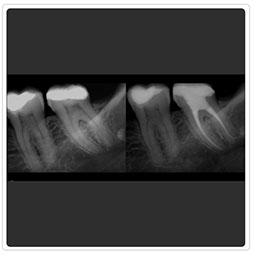

Radiografía Retroalveolar

Radiografía Control Endodoncia

Radiografía Intraoral

Radiografía Control de Implante